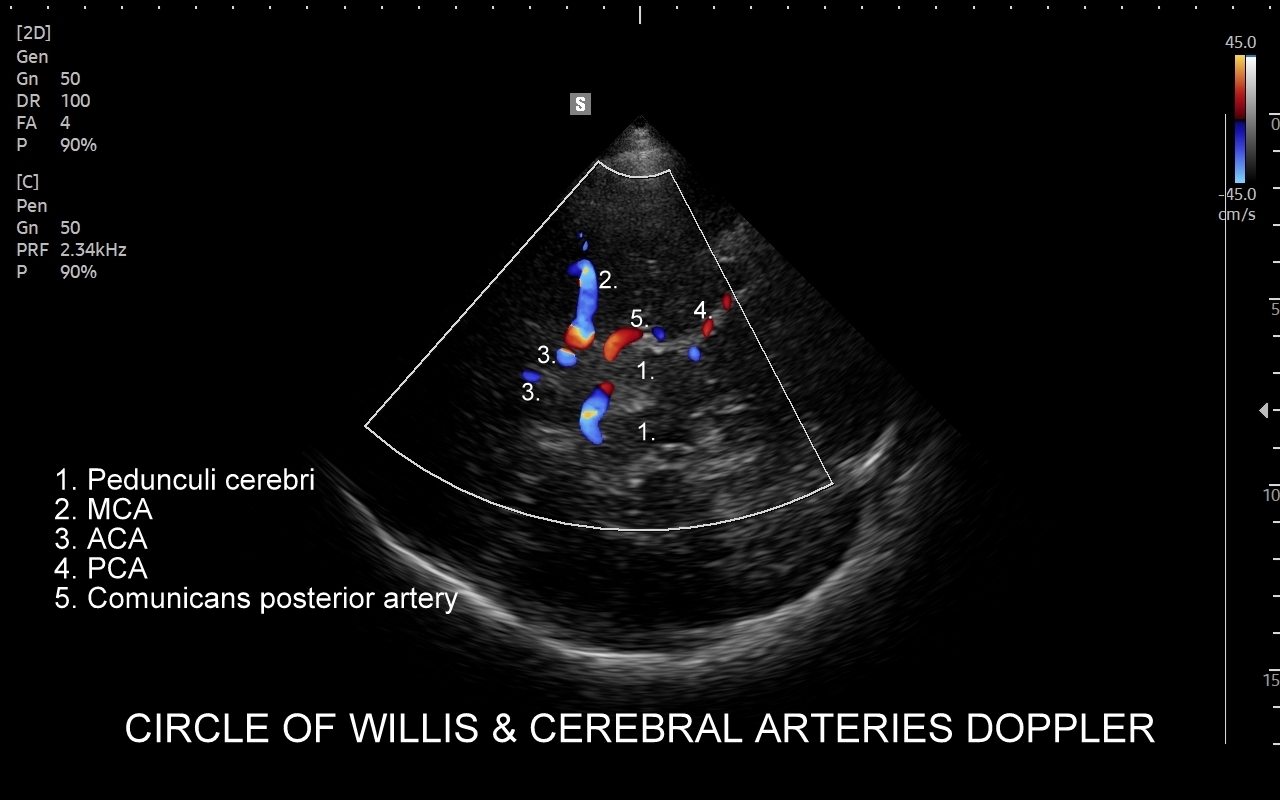

Badanie USG Doppler tętnic wewnątrzczaszkowych (ang. TCCD, transcranial color-coded Doppler), nazywane także Dopplerem przezczaszkowym jest naturalnym rozszerzeniem i uzupełnieniem badania dopplerowskiego tętnic dogłowowych zewnątrzczaszkowych. Badanie polega na obrazowaniu przy użyciu dedykowanej sondy poprzez tzw. okno skroniowe czaszki głównych naczyń tętniczych mózgu, tj. koła Willisa, tętnic mózgowych przednich, środkowych i tylnych po obu stronach. Badanie TCCD umożliwia wykrycie wybranych wewnątrzczaszkowych patologii naczyniowych takich jak tętniaki, malformacje naczyniowe, zwężenia i niedrożności poszczególnych tętnic mózgowych, spazm naczyniowy, a także pozwala na ocenę kierunku przepływy krwi w kole Willisa mózgu, co  jest przydatne przy diagnostyce zespołu podkradania lub w ocenie po przebyciu udaru mózgowego.